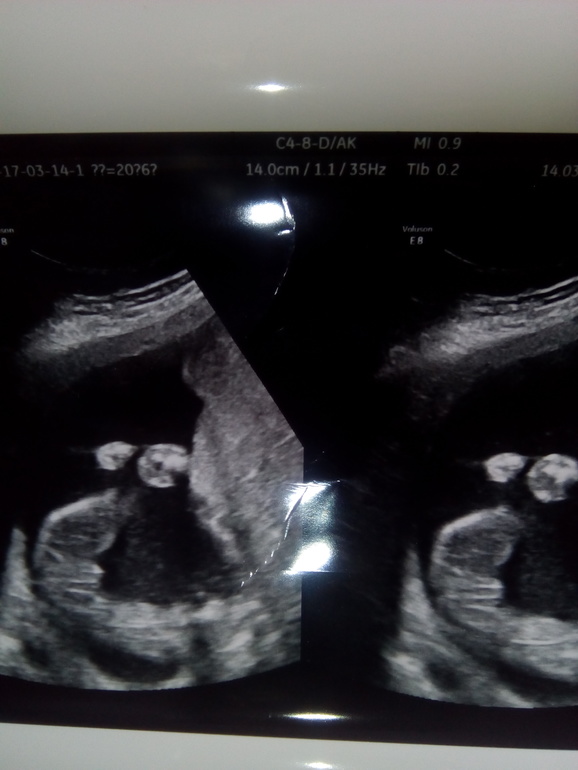

УЗИ 21 неделя.

УЗИ, КТГ, доплерПрошла я очередное плановое УЗИ.На праздники я заболела и это видимо отразилось на беременности.Весит мой малыш 353 гр.Все соответствует сроку.Но поставили многоводие,не тугое обвитие пуповины,увеличены лоханки и 1 степень зрелости плаценты.Предположили девочку.Я попросила фото пола,сама не разобралась,кому интересно прошу под кат.

но я честно ничего не понимаю по снимку, но пусть будет девочка))